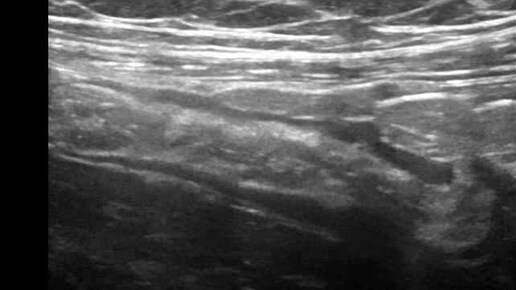

Видео к статье "Ультразвуковая диагностика дивертикулёза толстой кишки" https://dzen.ru/a/ZxDO7AgYcSelVXD-